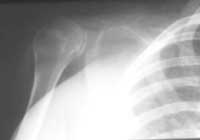

Se inicia tratamiento con calcitonina sin respuesta y la enfermedad progresa de modo que compromete la abducción del hombro. La evolución radiografía es la siguiente: en 1997 hay reabsorción del extremo distal de la clavícula, con imagen en punta de lápiz (Figura 5). En 1998: reabsorción del 90% de la clavícula y de la totalidad de la apófisis coronoides, el acromion y la glenoides. En 1999: compromiso completo de la clavícula (Figura 6). En el último control radiográfico, correspondiente a 2000, se encontró reabsorción en clavícula, glenoides, dos tercios de la escápula y la cabeza del húmero, con lesiones permeativas (Figura 7).

Figura 6. Se observa la ausencia de clavícula y parcial de la escápula.

Figura 7. Osteolisis masiva de la cintura escapular derecha.